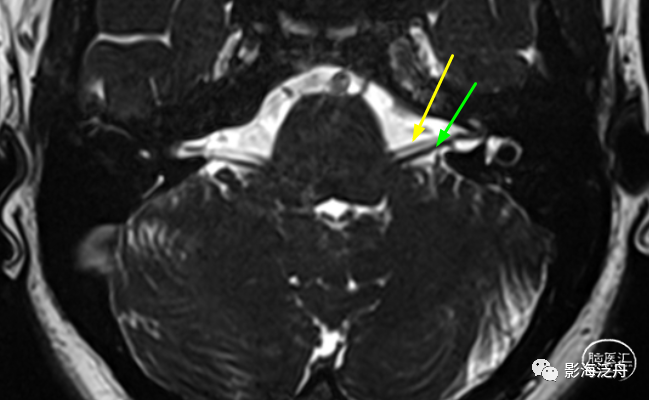

在轴位MR图像上观察并准确辨识出相应的神经和血管,常规的FSE T2WI也可以看到这些颅神经和血管,但不够清晰,尽量还是在更专业的3D重T2WI序列或3D B_FFE序列上观察,如下图↓

T2-TSE3D-RST-TRA成像是重T2成像,脑脊液呈高信号,三叉神经,面听神经和血管在脑脊液的高信号衬托下呈低信号可清晰显示,即使周围很小的血管分支也可能成像。

此外,T2-TSE3D-RST-TRA能对静脉以低信号成像,而且无须造影剂,通过多层面分析可确定压迫血管的来源,与常规磁共振技术相比不仅扫描速度成倍提高,并且通过三维薄层技术弥补对比度和分辨率的损失,获得高分辨率、高信噪比的图像,是检查脑神经和血管成像的最佳技术。